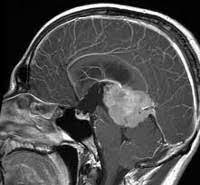

Особое место отводится комплексной диагностике, которая для точности результата должны быть максимально детализированной и всесторонней. Для определения локализации и размеров образования, стадии развития и степени его распространения, выявления метастаз, проводится инструментальное обследование, включая использование рентгенографии, КТ, МРТ, сцинтиграфии, УЗИ. Выполняется лабораторная диагностика, позволяющая выявить в моче уровень катехоламинов, повышающихся при наличии ганглионейробластомы. Метастазы помогает также обнаружить пункция лимфатических узлов. Окончательный диагноз базируется на информации, полученной после микроскопического исследования фрагмента образовании, взятого в ходе биопсии.